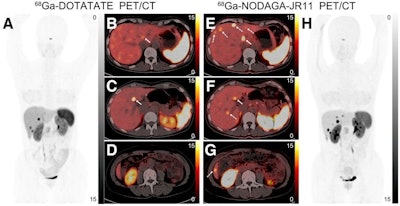

The first 48 patients enrolled in the trial (out of 100 planned) between August 2020 and November 2021 received Ga-68 DOTATATE on the first day and experimental Ga-68 NODAGA-JR11 on the second day. Whole-body PET/CT scans were performed between 40 and 60 minutes after injection, with the researchers then comparing normal-organ uptake, lesion numbers, lesion uptake, and sensitivity between the tracers.

Overall, Ga-68 NODAGA-JR11 demonstrated lower background uptake in normal organs and detected significantly more liver lesions than Ga-68 DOTATATE (673 vs. 584, p = 0.002), the researchers found.

"The results favor Ga-68 NODAGA-JR11 because of a higher detection ability and better image contrast for liver metastases," Lin and colleagues concluded.